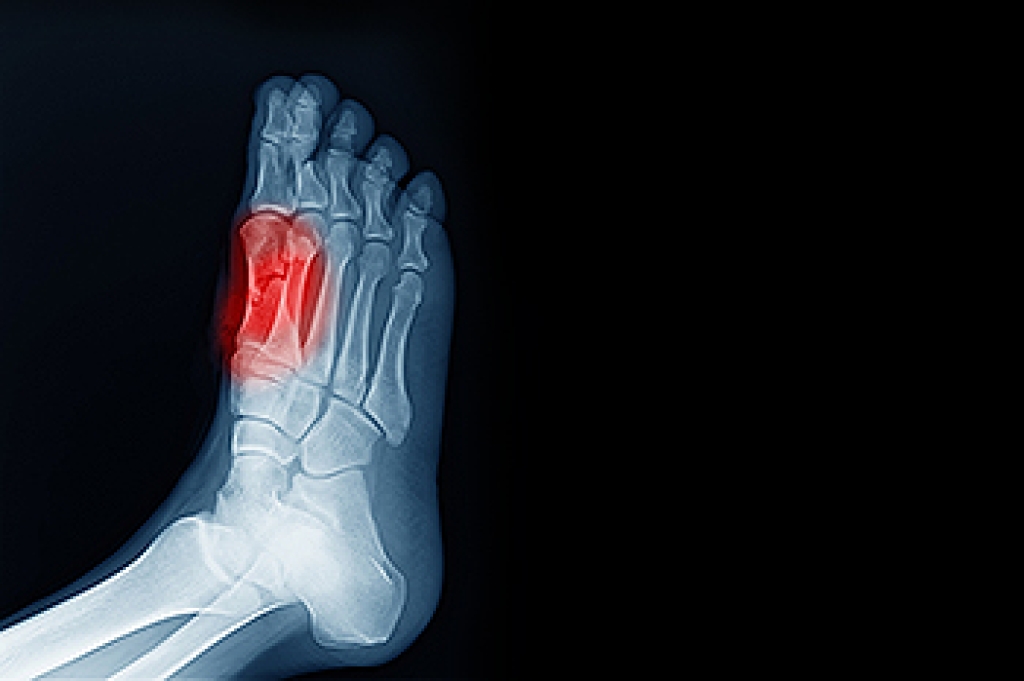

Morton’s neuroma is a painful condition that affects nerves in the feet, most commonly between the third and fourth toes. It occurs when the nerve becomes thickened or compressed, often due to repetitive pressure or irritation. Causes include wearing tight or high heeled shoes, engaging in high impact sports, or abnormal foot mechanics. Symptoms typically involve sharp or burning pain in the ball of the foot, tingling, numbness, or a feeling of a pebble under the foot. Risk factors include foot deformities, repetitive activity, and wearing improper footwear. A podiatrist can help by diagnosing the condition, providing custom orthotics, recommending footwear modifications, and offering noninvasive treatments to reduce pain. If you have pain between your toes, it is suggested that you consult a podiatrist for a proper diagnosis and treatment.

Morton's neuroma is a painful foot condition that commonly affects the areas between the second and third or third and fourth toe, although other areas of the foot are also susceptible. Morton’s neuroma is caused by an inflamed nerve in the foot that is being squeezed and aggravated by surrounding bones.